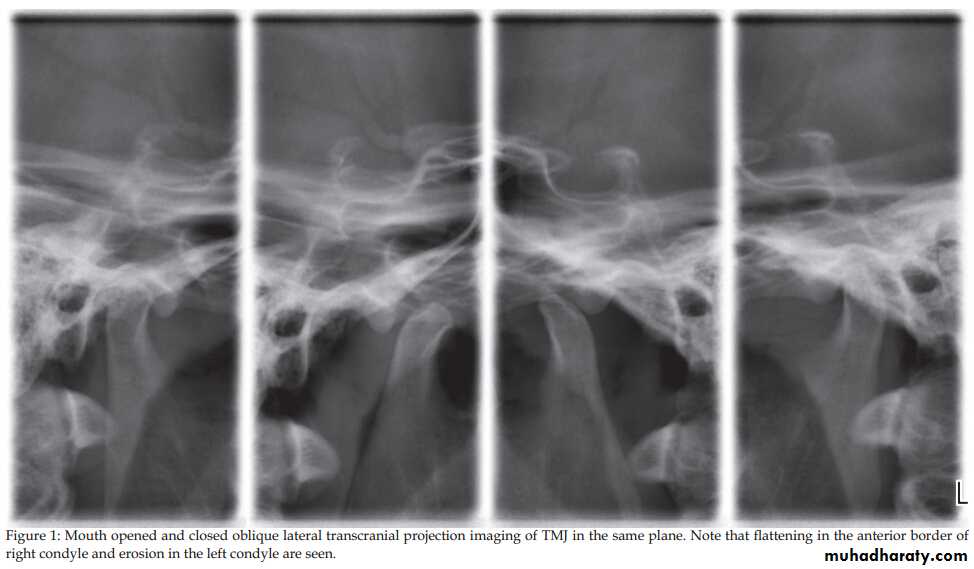

1. OPG & Transcranial oblique lateral view.

Radiology

Dr. Mohammed Amjed Alsaegh, 2021

14